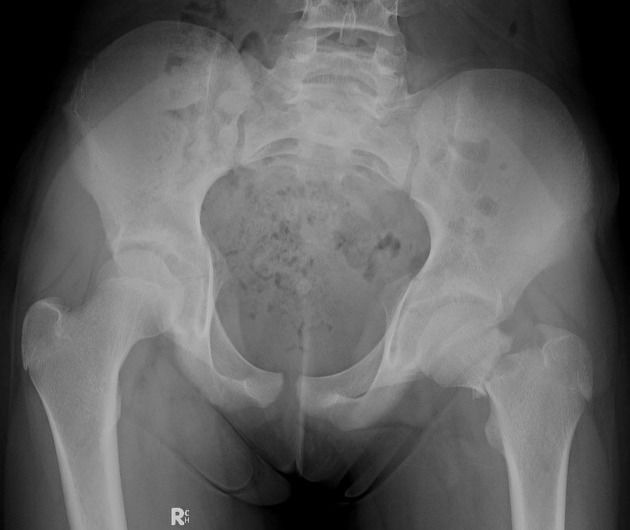

Q.11. What's the Xray finding?

Correct Answer : B